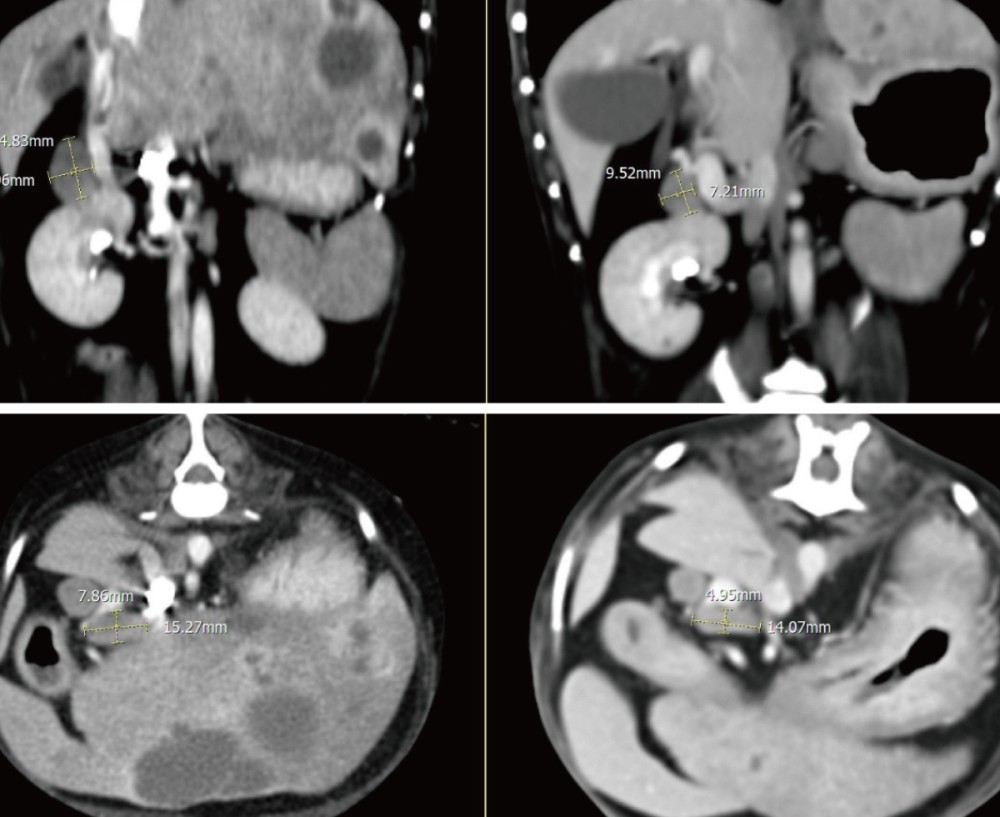

추가로 CT를 시행하였으며, 그 결과 간 실질 내 다발성 낭성 병변과 함께 췌장 석회화, 총담관 확장, 담석이 확인되었습니다.

실제로 추적 CT에서도 간 내 낭성 병변의 크기가 뚜렷하게 감소하고 림프절 크기 또한 감소하여 처치에 대한 반응이 명확하게 확인되었습니다 .

▲ 좌측 내측엽과 가측엽에 위치하던 cystic lesion의 크기 뚜렷한 감소 및 불규칙한 변연으로 변화

▲ 이전 검사에서 뚜렷하게 종대되어 관찰되었던 간 림프절 크기 감소

▲ 대동맥 림프절의 크기 감소​